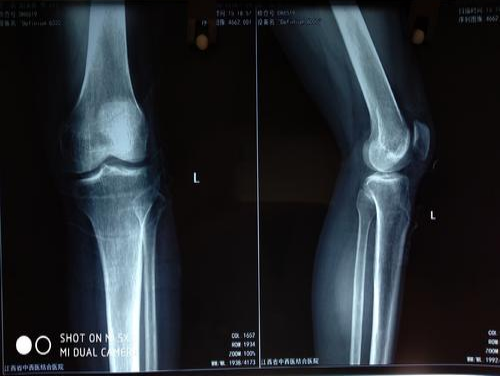

3.X线表现

(1)疾病初期:关节软骨轻度退变,X线检查可以正常。

(2)进行期:关节间隙变窄、软骨下骨质硬化、关节边缘尖锐并有骨赘形成、骨端部变宽、关节面不规则、关节畸形等。

(3)晚期:软骨破坏加剧,关节间隙明显变窄,关节边缘骨质硬化程度增加。如果只出现关节软骨病损或出现X线片的增生性改变,而尚无关节炎症状则称为增生性改变、退行性改变,属生理性改变的范畴。